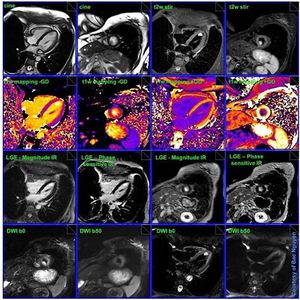

Cardiac tumor CMR

Multiparametric CMR of cardiac tumor (based on anatomical, functional & quantitative MR imaging). Advanced CMR techniques like DWI of the heart and T1 mapping before and after the administration of Gd.